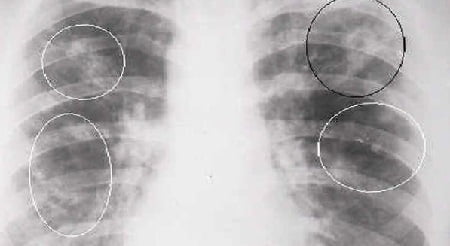

Диагноз этого опасного заболевания ставит только врач. Для определения болезни необходимо рентгенологическое исследование. Также, для диагностики туберкулёза лёгких исследуют мокроту на наличие микробактерий туберкулёза. На туберкулёз у детей может указывать положительная проба Манту. В некоторых случаях, для достоверности берется анализ крови.